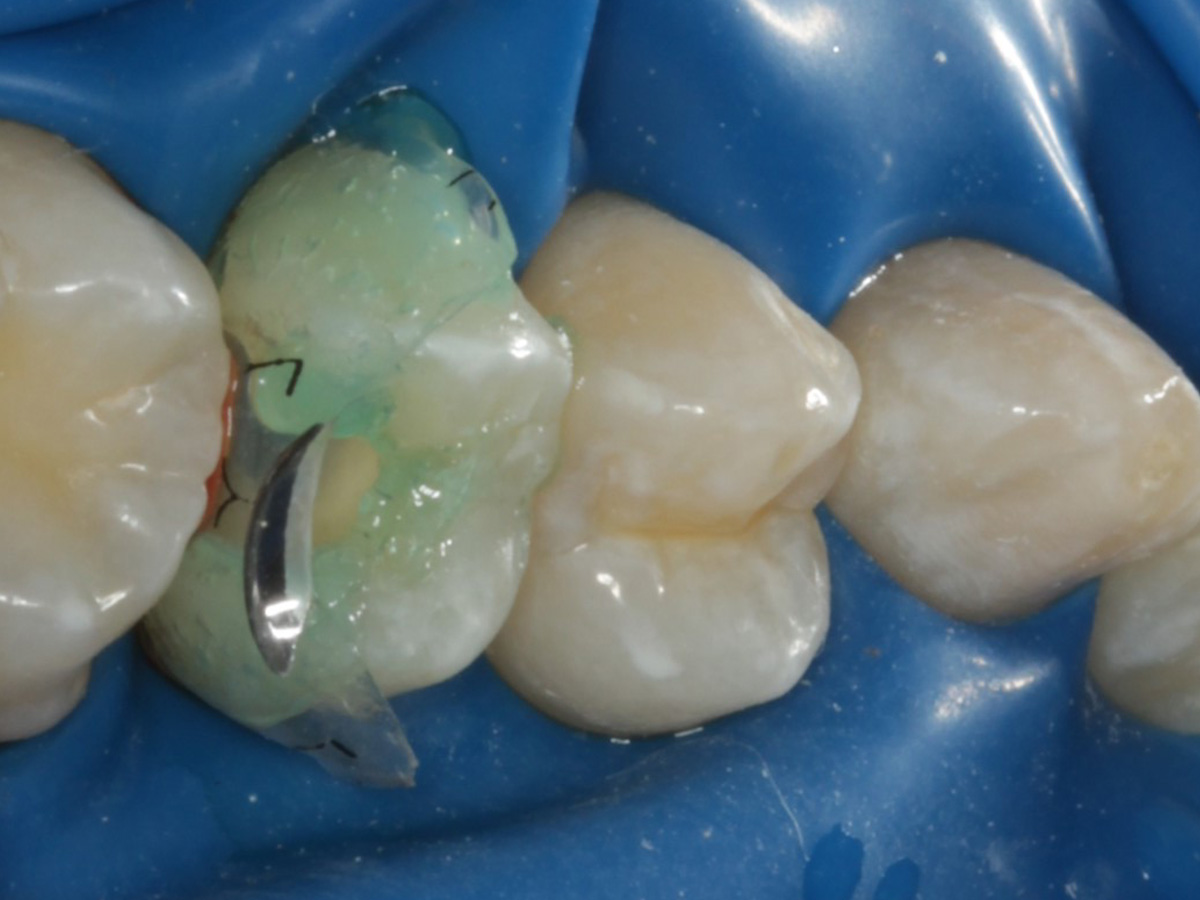

Abbildung 3

Quadrantenisolierung mit Kofferdam (x-heavy)